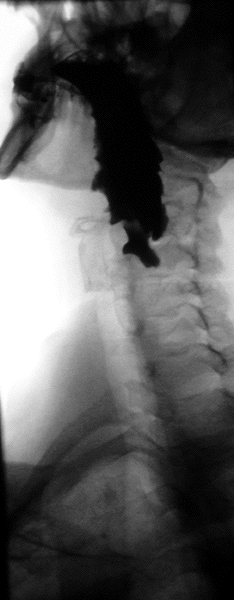

En anatomie, un diverticule de Zenker est un diverticule (une poche) de pulsion qui se forme au-dessus du sphincter œsophagien supérieur entre le faisceau thyroïdien du muscle constricteur inférieur et le faisceau cricoïdien du muscle constricteur inférieur (aussi appelé muscle cricopharyngien).

Radiographie où on voit une diverticule de Zenker.

Le diagnostic est radiologique. Aujourd'hui l'imagerie de première intention à effectuer est un scanner cervico-thoraco-abdomino-pelvien avec opacification digestive haute ainsi qu'injection de produit de contraste. Le transit œso-gastro-duodénal historiquement utilisé qui visualise le diverticule sous forme d'une image d'addition du tiers supérieur de l'œsophage n'a pratiquement plus d'indication à l'heure actuelle en raison de la meilleure précision de l'examen TDM[1].